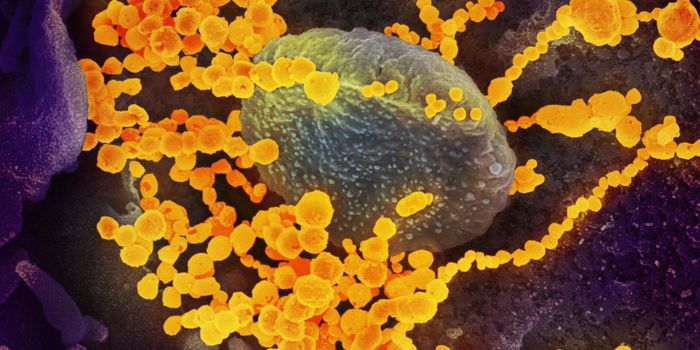

AUG 19, 2020Cell & Molecular BiologyAs the pandemic virus, SARS-CoV-2 continues to cause tens of thousands of new cases of COVID-19 every day in the United ...

APR 27, 2020MicrobiologyThe pandemic virus that causes COVID-19 has now infected nearly 3 million people, and killed over 200,000.

MAY 10, 2021MicrobiologyThe pandemic virus SARS-CoV-2 has changed the world in devastating ways, taking hundreds of thousands of lives & new var ...